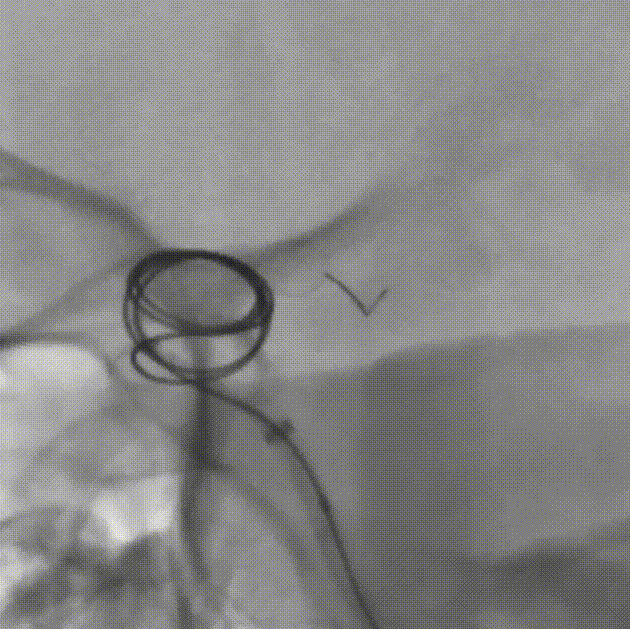

选用YonFlow®血流导向密网支架 4.75*30mm、弹簧圈 12×40,进行密网支架结合弹簧圈栓塞。

YonFlow®血流导向密网支架释放。

1、该例患者的大型动脉瘤位于左侧颈内动脉眼动脉段,瘤颈较宽(动脉瘤最大直径11.3mm,瘤颈8.5mm),且位于靠近虹吸弯的眼动脉段,给FD的选择带来一定困难;瘤颈近端与远端的载瘤血管直径差异较大(1mm),为保证支架充分贴壁,对支架的选择要求较高。术者选择应用一款可100%回收的钴铬合金材质的FD——YonFlow®血流导向密网支架,钴铬合金材质使得支架网丝相对镍钛更硬,释放后短缩程度小,尺寸选择相对容易,定位更精准。100%可回收的创新型设计使得支架在完全推出后依然可回收并重新精准定位,从而确保支架的良好贴壁。

2、支架网丝的远端为球形头端设计,可有效避免支架头端对血管壁及穿支的损伤,提高了支架输送及释放时的远端安全性。该款支架同时具备良好显影性,在透视情况下可完整体现支架的结构,使释放时的判断及调整更加可控。